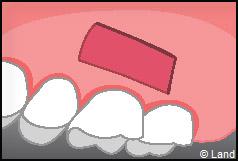

LES TECHNIQUES AVEC APPORT DE GENCIVE OU « GREFFE DE GENCIVE » :

Elles font appel à un prélèvement sur le patient à un endroit où elle est en excès, qui est ensuite posé sur la récession.

Les greffes épithélio-conjonctives :

Elles sont pratiquées pour des zones non esthétiques de la cavité buccale, à cause de l’aspect « rustine» que la cicatrisation leur confère.